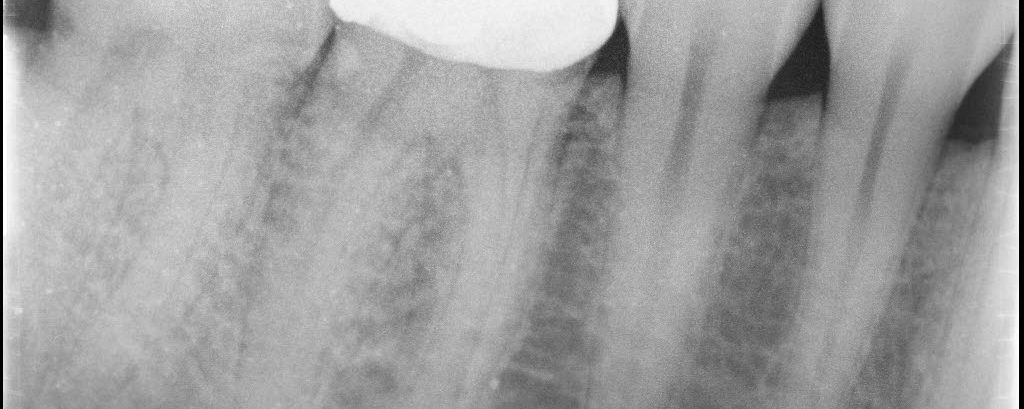

42 yom. Symptomatic Partially Vital Pulp. No response to cold. Upon access, I observed hyperemic tissue in MB1 and partially vital tissue in the rest of the canals. 2-1-2 MB root system. 1 visit. Asymptomatic and functional at the follow-up visit.